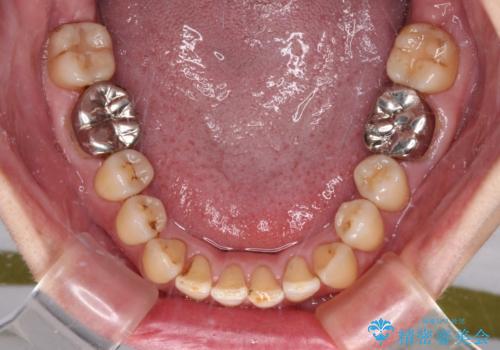

舌のトレーニングをしっかりと行ってくださり、10ヶ月で希望通りの歯列となりました。

日頃から飲まれる飲み物の影響で着色しやすいため、来院の度に着色除去のクリーニングも行っていました。